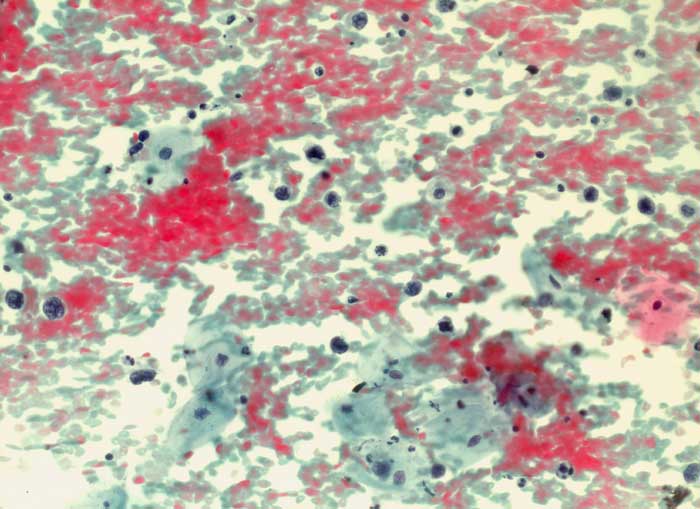

Maligne Lymphome der Zervix sind selten. Meist handelt es sich um die Manifestation eines generalisierten Lymphoms in der Zervix und nicht um ein primäres Zervixlymphom. Beim diffusen grosszelligen B-Zell Lymphom lassen sich einzeln liegende atypische blastäre Zellen nachweisen, die mindestens zweimal so gross sind wie kleine Lymphozyten. Die Kerne sind vesikulär und enthalten einen solitären zentralen oder mehrere periphere Nukleolen. Ausserdem sind Apoptosen, kleine Lymphozyten, Plasmazellen und Makrophagen zu sehen. Der Ausstrichhintergrund enthält oft Detritus.